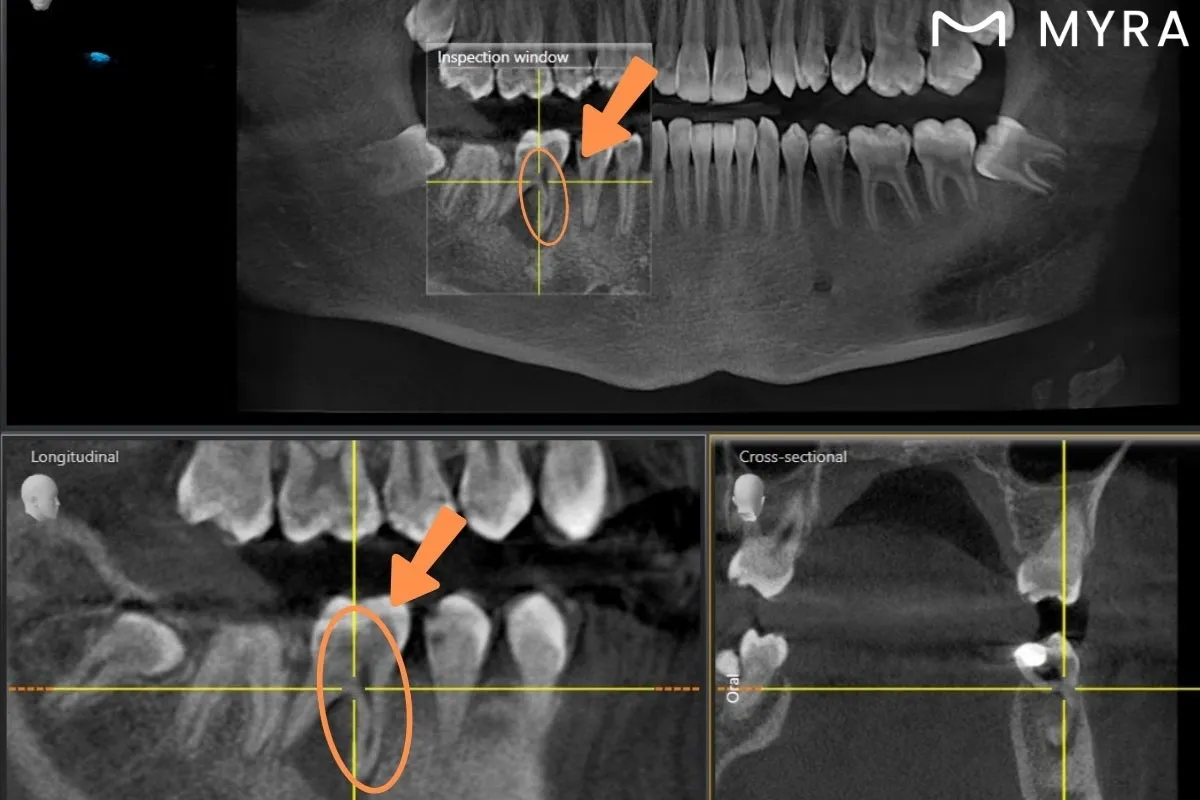

8. Radiological Findings: Radicular Cyst or Granuloma

In some cases, a failed RCT may be asymptomatic. In these situations, routine dental check-ups using X-rays may reveal the failure. An infection at the tooth root is diagnosed radiologically as a cyst or granuloma. Asymptomatic failures can spread the infection and lead to more serious issues. Radicular cysts are prone to continuous growth.